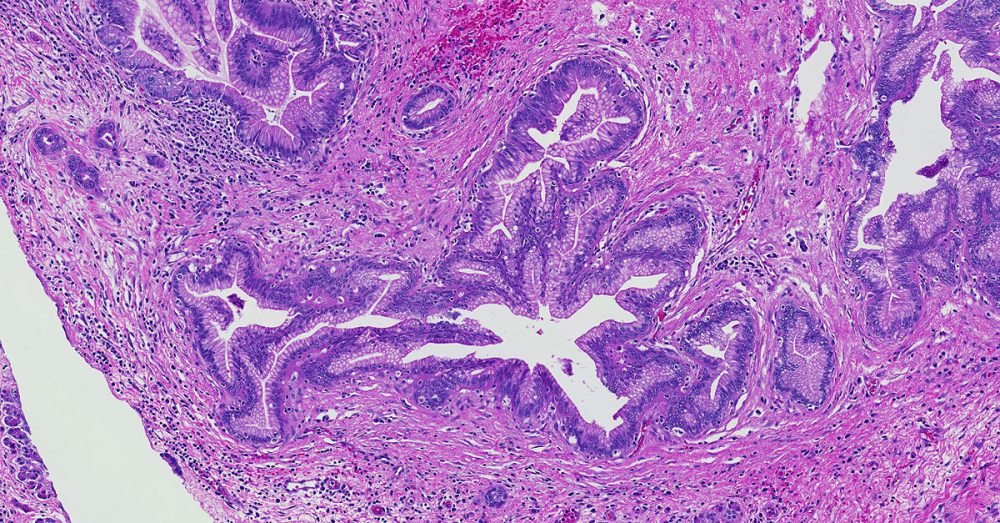

Low-grade pancreatic intraepithelial neoplasia encompasses three older terms- PanIN-1A, PanIN-1B and PanIN-2.